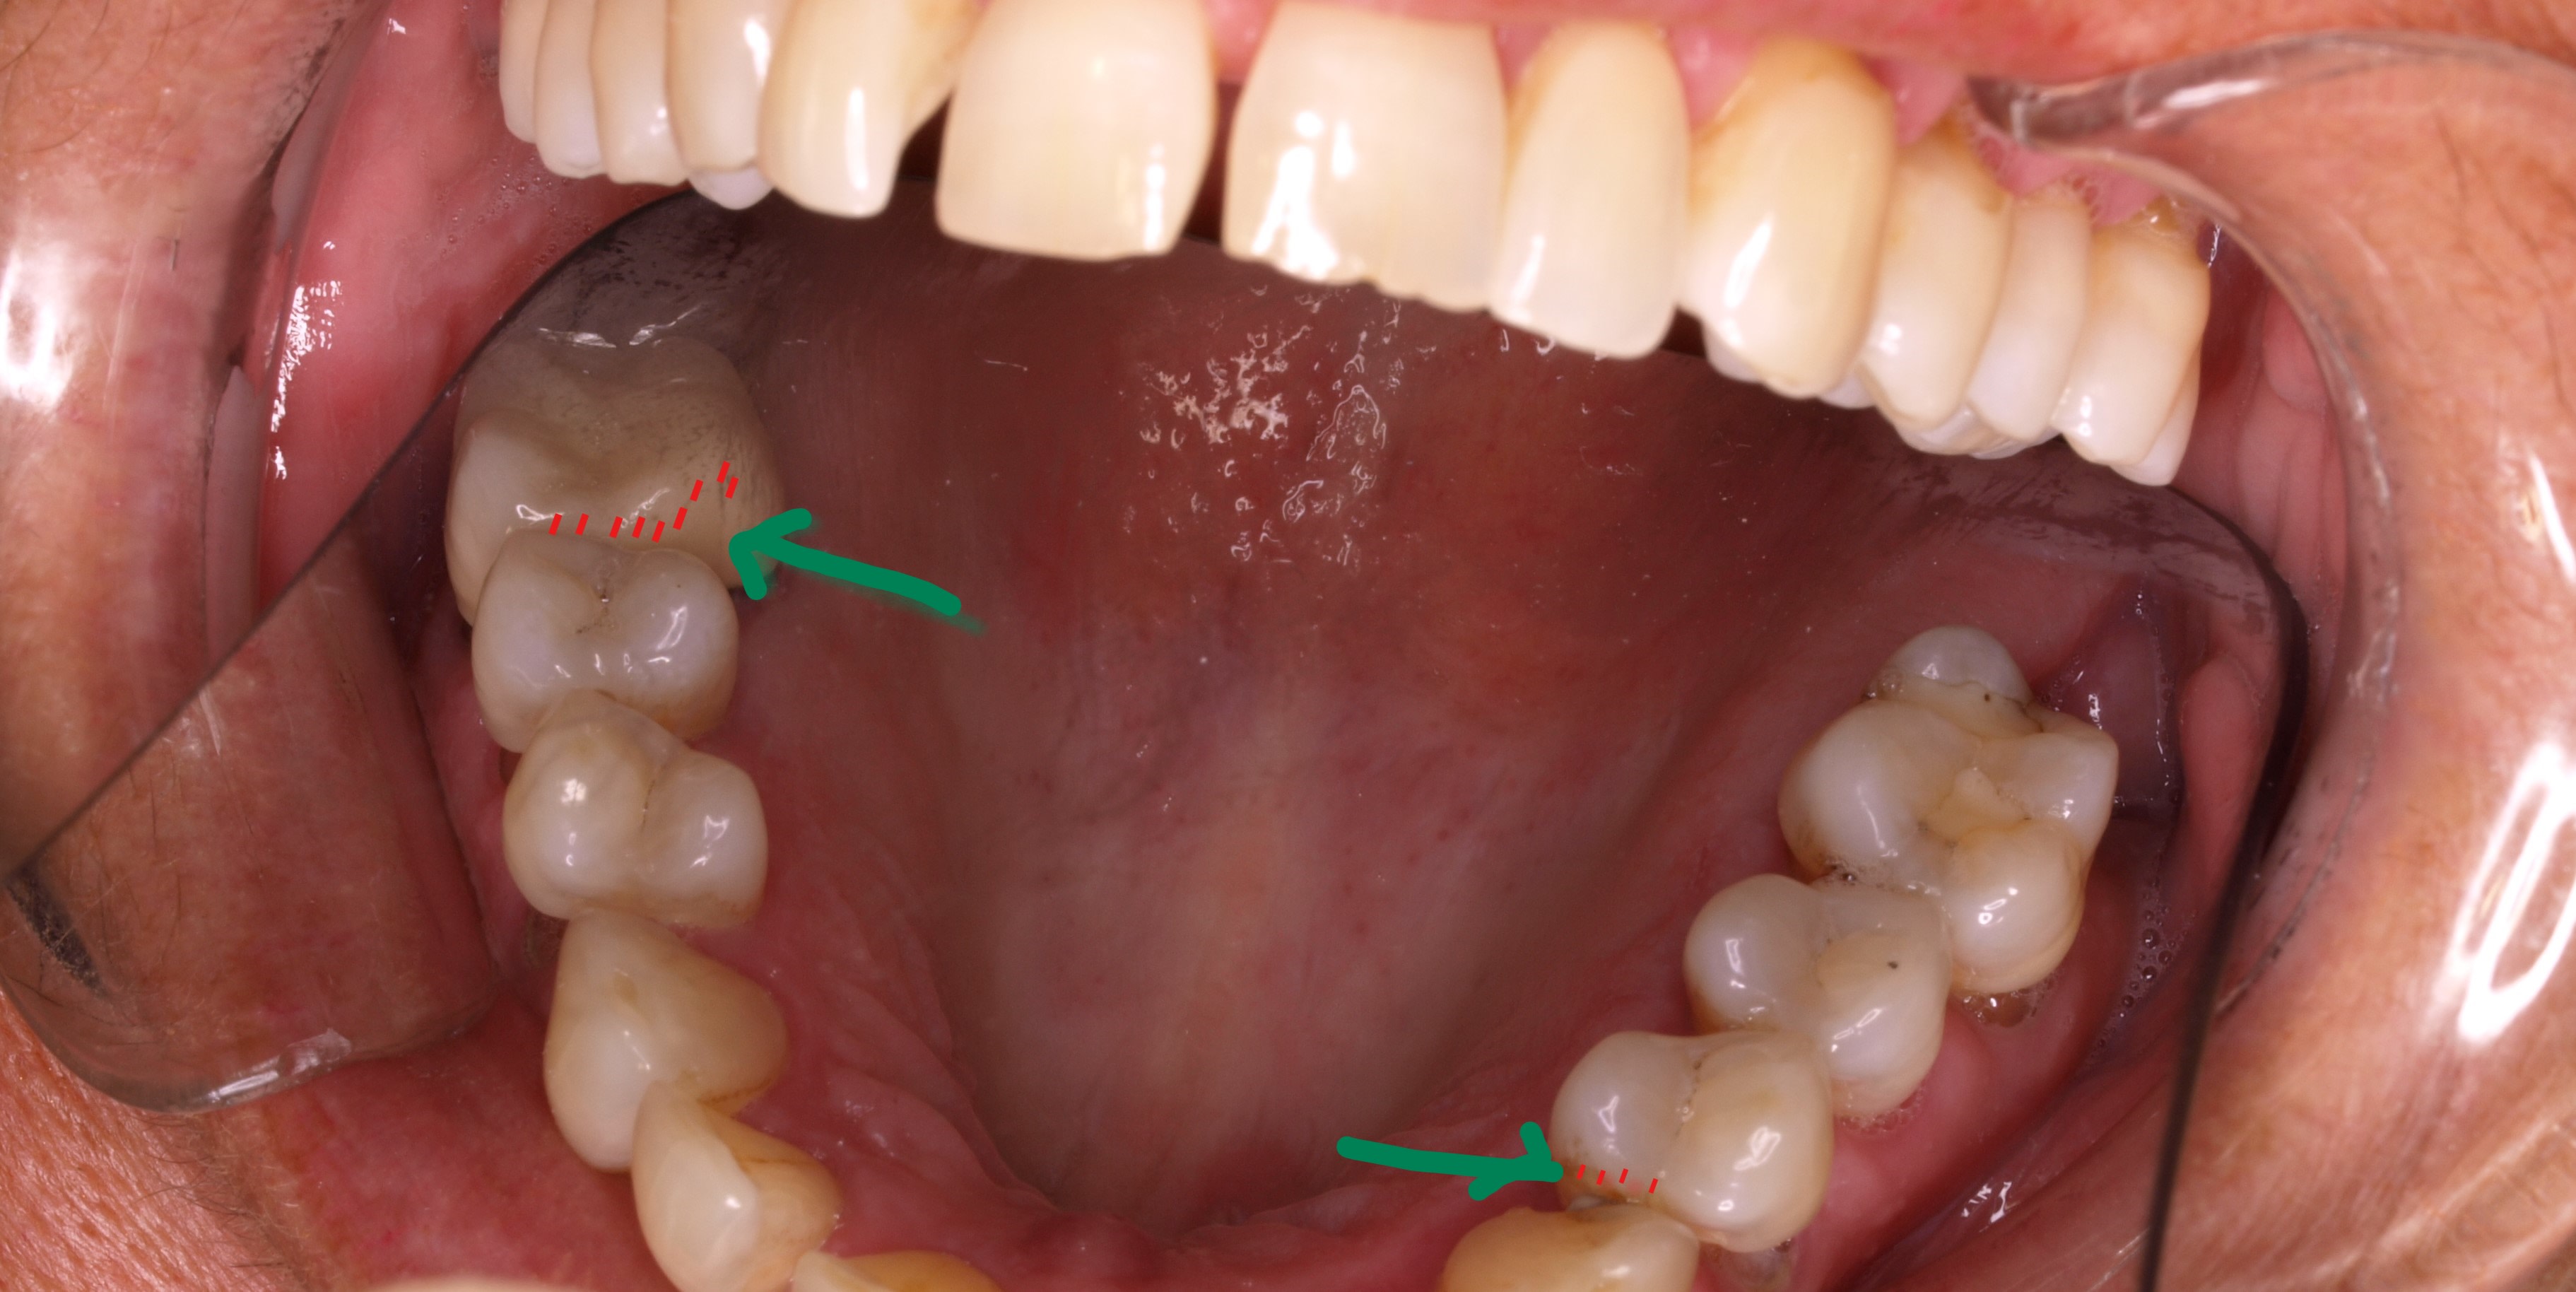

bon regardes ce cas .

2016 : il se plaint de bourrages alimentaire secteur 10 + des petites fractures sur gros compo .

pas de pb , que je lui dis , j'va te couronner la pm mon grand tu vas etre bien comme tout .

2019 : houuuuu l enc . mais pourquoi ? qu est ce que j ai fait pour que ça merde autant sur ma 15 ( perte de contact ) ?

Bb hb8ftu - Eugenol

et donc je cherche en bas secteur 30 . et voilà . j avais pas vu , ou tout au moins je manquais encore de conviction quand au décalage des crêtes marginales .

tu vois la crête mesiale de 6 en fer ? avec la mega facette d usure en proximal ?

et bien au fur et a mesure des usures dentaires , le metal lui ne s est pas usé , et ça a créé une prématurité .

or une prema sur une crête , ç est un drame pour le mvt OIM / ORC .

donc qu est ce qu il fait le gonz ? eh bien il va se décontracter , du coté opposé pour eviter cette prema .

il va du coté opposé , tout en reculant son ATM coté droit , pour espérer faire avancer son ATM coté gauche . et anisi , il évite cette putain de crête .